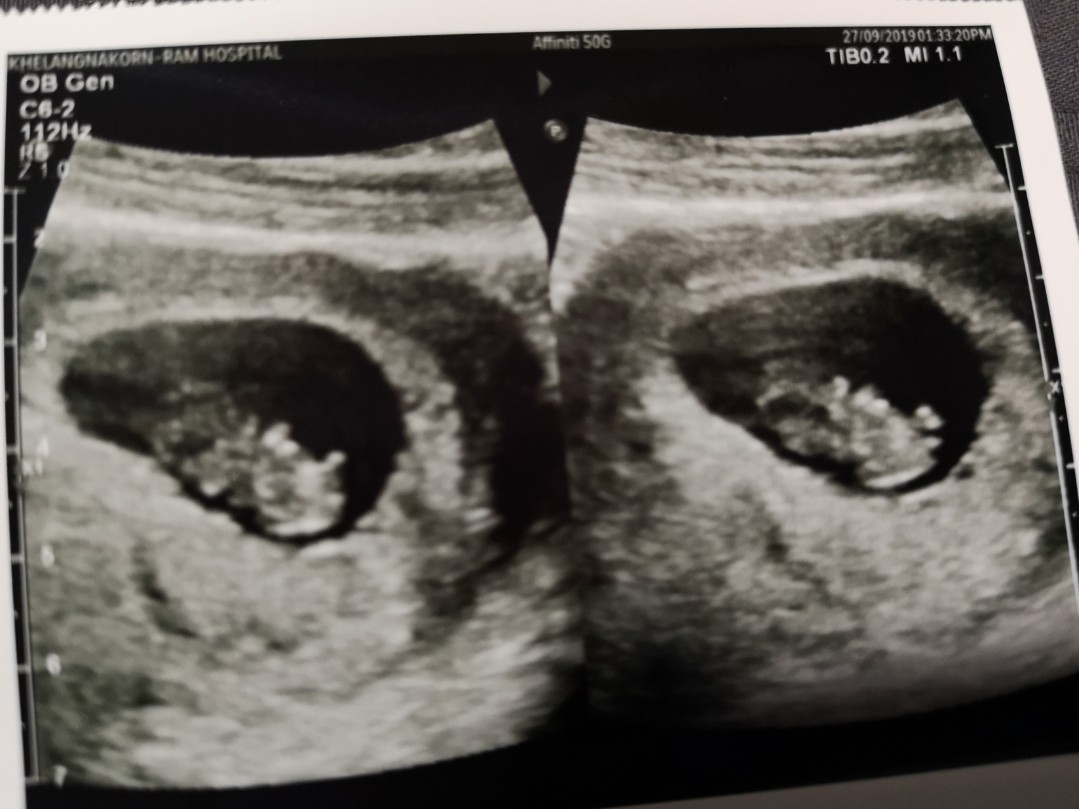

ไปซาวมาเมื่อวาน 10w4d

13 วีคจ้า

13วีคค่ะ